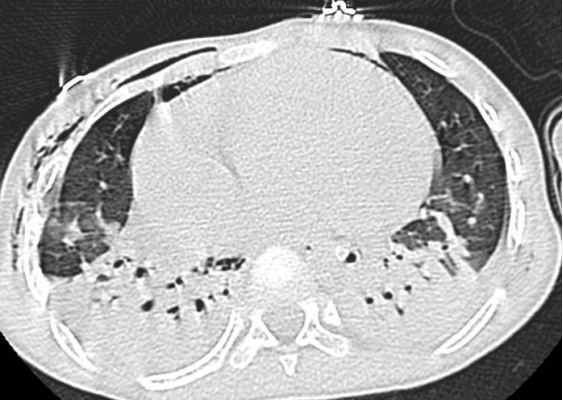

隨著冬季流感高發(fā)期的到來(lái),兒童呼吸道感染病例顯著增多。貴陽(yáng)市公共衛(wèi)生救治中心重癥醫(yī)學(xué)科(大營(yíng)路院區(qū))近日成功救治了一名危重癥甲流患兒,經(jīng)過(guò)長(zhǎng)達(dá)24天的全力搶救與精心護(hù)理,孩子最終轉(zhuǎn)危為安,康復(fù)出院。 這名6歲患兒因持續(xù)高熱、呼吸急促被緊急送醫(yī)。入院時(shí),患兒體溫高達(dá)40℃,血氧飽和度僅80%,胸部CT顯示雙肺多處感染病灶,病情急速進(jìn)展,生命垂危。 時(shí)間就是生命。重癥醫(yī)學(xué)科陳佳主任帶領(lǐng)醫(yī)療團(tuán)隊(duì)迅速研判,果斷為患兒實(shí)施氣管插管,并啟動(dòng)俯臥位通氣、支氣管鏡灌注等關(guān)鍵治療。護(hù)理團(tuán)隊(duì)24小時(shí)不間斷監(jiān)測(cè)生命體征,精細(xì)化氣道管理,積極預(yù)防并發(fā)癥,同時(shí)給予患兒心理安撫與親情式陪伴。 在醫(yī)療與護(hù)理團(tuán)隊(duì)的緊密協(xié)作下,患兒熬過(guò)了最危險(xiǎn)的階段,肺部感染逐漸吸收,順利脫離呼吸機(jī),身體各項(xiàng)機(jī)能穩(wěn)步恢復(fù)。出院當(dāng)天,患兒家屬將一面錦旗送到醫(yī)護(hù)人員手中,眼中含淚連聲道謝。這面錦旗,不僅代表著一個(gè)家庭的感激,更是對(duì)醫(yī)護(hù)團(tuán)隊(duì)專(zhuān)業(yè)堅(jiān)守與生命至上的深深認(rèn)可。 溫馨提示:冬季是流感高發(fā)期,請(qǐng)注意做好個(gè)人防護(hù),保持室內(nèi)通風(fēng),勤洗手,必要時(shí)接種流感疫苗,同時(shí)也提醒廣大家長(zhǎng),流感高發(fā)季節(jié),若孩子出現(xiàn)持續(xù)高熱、呼吸急促、精神萎靡等癥狀,須及時(shí)就醫(yī)。